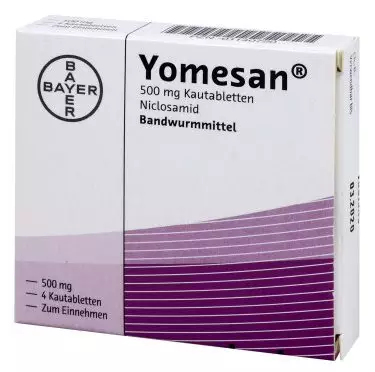

Niclosamida: ¿Qué es y para qué sirve?